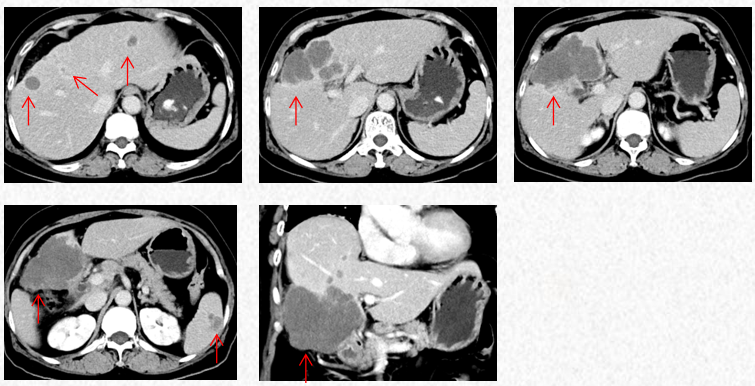

2023-5-22复查胸腹CT图片,疗效评估为SD,出现轻度双上肢麻木,可耐受。

2023-5-22胸腹CT:肝肿物最大横截面积86*58mm,脾脏转移瘤(19*12mm)